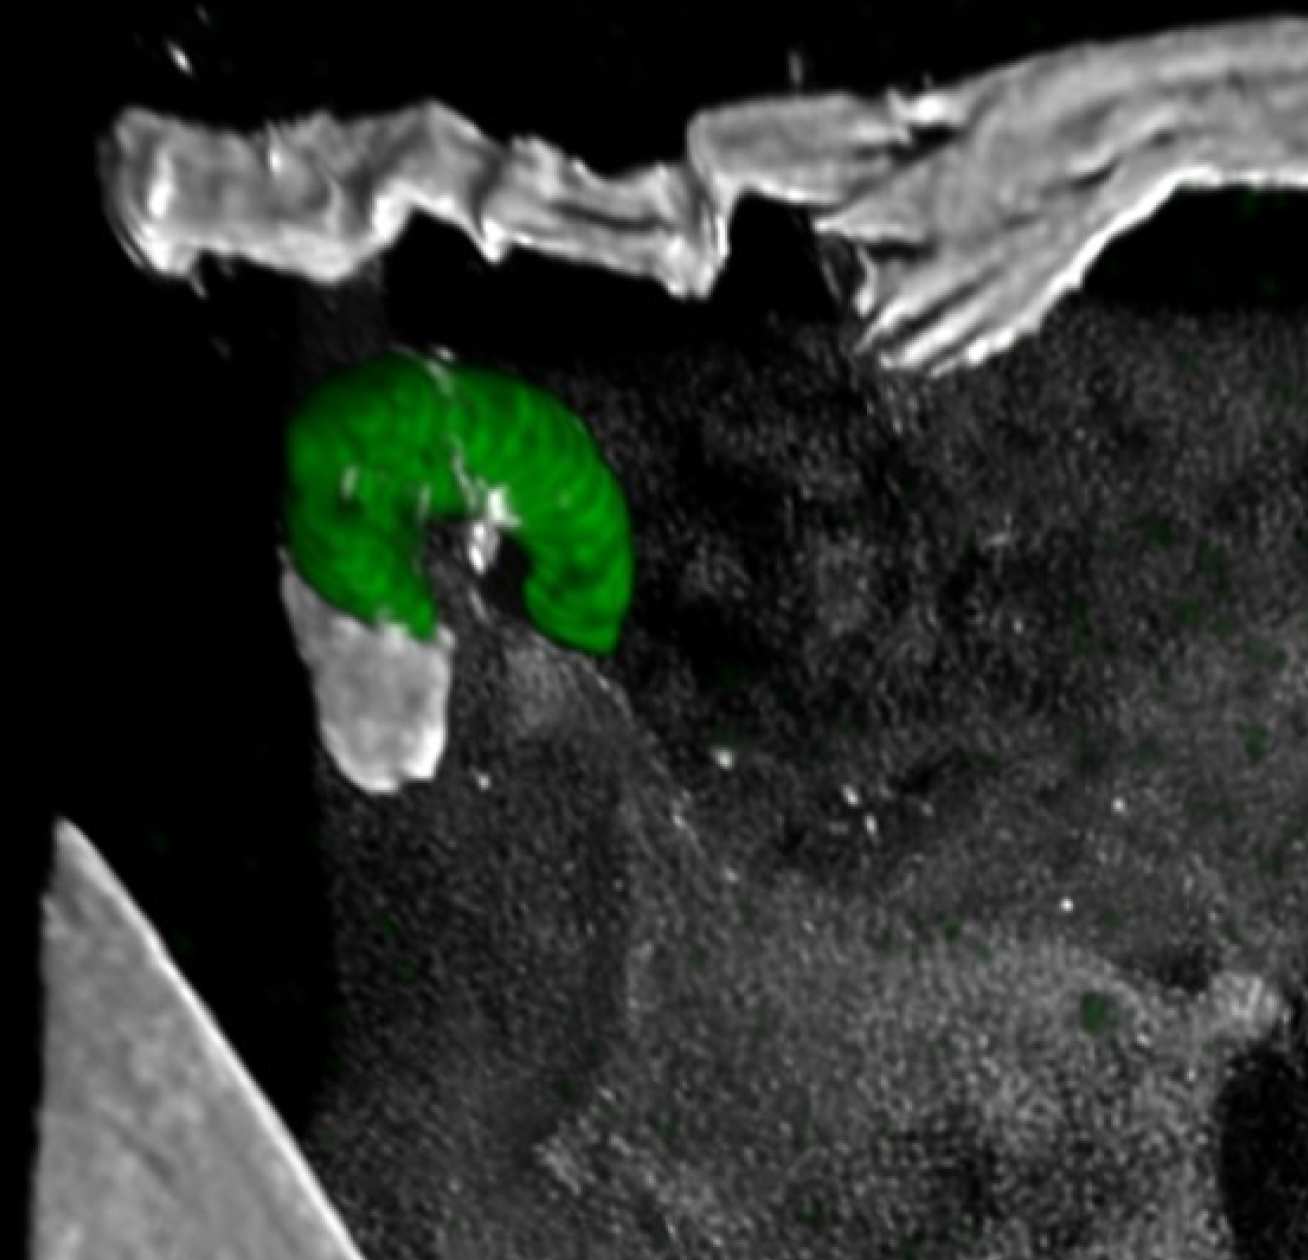

A green crescent shape (the dying parasite) inside a cell

A malaria parasite being attacked by the mosquito immune response as it passes through a gut cell. This parasite has not managed to fool the mosquito immune response and it will now be killed

There, it infects the gut tissue where it matures for several days before it is ready to infect a human when the mosquito bites again. But for the parasite to infect the gut tissue it must first endure the mosquito’s immune response.

Now, researchers at Imperial have discovered a molecule, named PIMMS43, on the surface of the parasite that helps it evade the immune system of the mosquito. The team then produced antibodies that could block the action of PIMMS43 and tested their ability to disrupt parasite transmission.